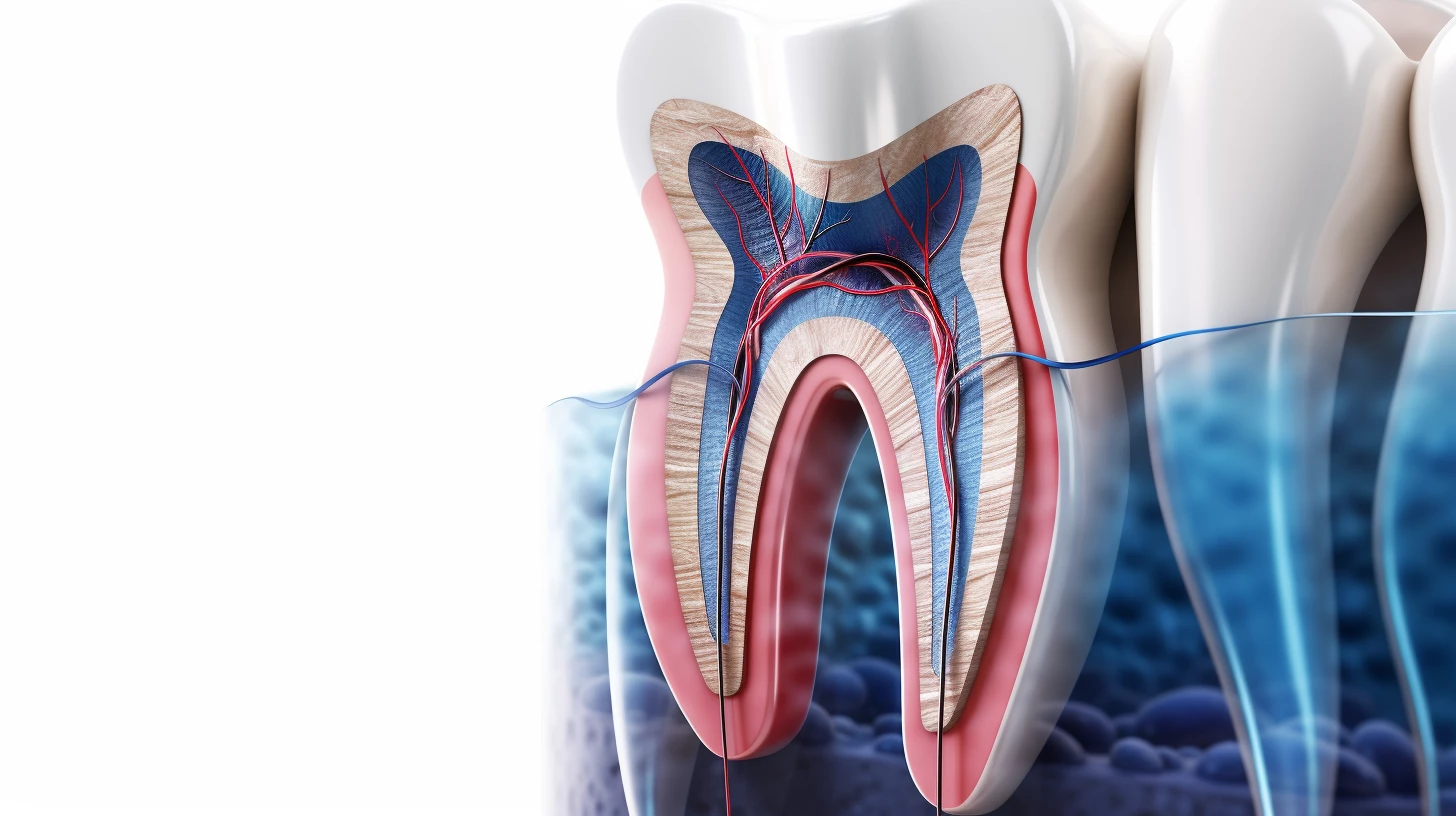

Анатомия корневых каналов — это сложная и разнообразная структура, которая по-разному проявляется в каждом зубе. Каждый корневой канал представляет собой деликатную систему, состоящую из мягких тканей, кровеносных сосудов и нервов. Правильное понимание этой анатомии всегда служило ключом к эффективному лечению зубов, позволяя стоматологам проводить точные манипуляции, необходимые для успешного лечения.

Каждый зуб состоит из коронки, видимой части зуба, и корня, расположенного в челюстной кости. Внутри зуба находится пульпа, содержащая нервы и кровеносные сосуды. Именно в пульповой камере начинаются корневые каналы, которые проходят через корень. Количество корневых каналов может значительно варьироваться в зависимости от типа и местоположения зуба. Резцы и клыки обычно имеют по одному корневому каналу, в то время как премоляры и моляры могут иметь несколько.